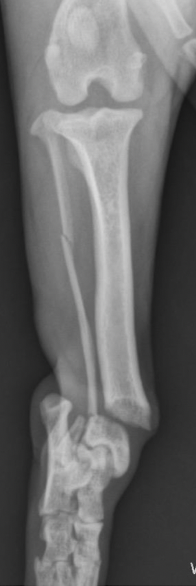

plate rod fixation is — with —

IM pin with bridging plate

the IM pin will help align bone and maintain bone length while increasing resistance to bending

plate/rod fixation will reduce strain on the plate by —. and will increase fatigue life of plate by —

2x

how big of IM pin or plate/rod fixation

A

35-40% of medullary cavity

allow screw placement

avoids excessive rigidity

normograde insertion (top down)

how many screw for plate/rod fixation

4 cortices on each side of fracture at least

IM pin and plate, pin can get in the way and need to use monocortical screws

— is a good fixation technique for comminuted diaphyseal fractures

Plate/rod

IM pin and plate